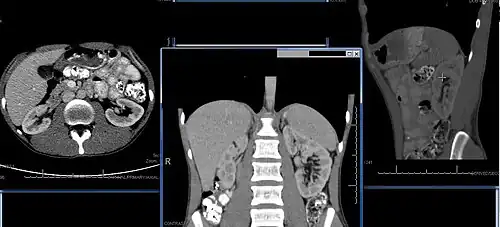

Imaging

Renal ultrasonography is essential in the diagnosis and management of kidney-related diseases.[48] Other modalities, such as CT and MRI, should always be considered as supplementary imaging modalities in the assessment of renal disease.[48]